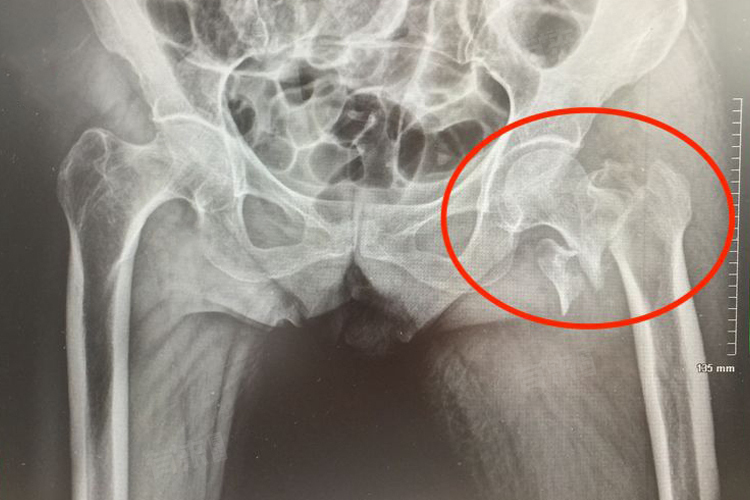

左侧股骨颈骨折是一种较为常见且严重的骨骼损伤,其发生并非偶然,而是多种复杂因素共同作用的结果,如直接暴力、间接暴力等。此类情况的治疗方法包括紧急固定、手术治疗等。

2、间接暴力:在日常生活中,老年人在行走时不慎滑倒,身体扭转,下肢突然外展、内收或过度屈伸,这种间接的外力传导至股骨颈,可能引发骨折。对于间接暴力造成的骨折,若骨折移位不明显,可先采用保守治疗。患者需卧床休息,患肢进行皮肤牵引或骨牵引,维持骨折部位的稳定性,促进骨折愈合。定期进行影像学检查,观察骨折愈合情况。若骨折移位明显,或患者身体状况允许,应优先考虑手术治疗,通过手术复位并使用螺钉、钢板等内固定器械固定骨折断端,以恢复股骨颈的正常结构,减少骨折不愈合及股骨头坏死等并发症的发生风险。

- 股骨颈骨折后,股骨头的血液供应受到影响。由于股骨头的血液供应主要依赖于股骨颈周围的血管,骨折可能导致血管断裂或损伤,使股骨头供血不足。若血液供应无法及时恢复,长期缺血会导致股骨头坏死,进一步加重疼痛,影响髋关节功能。